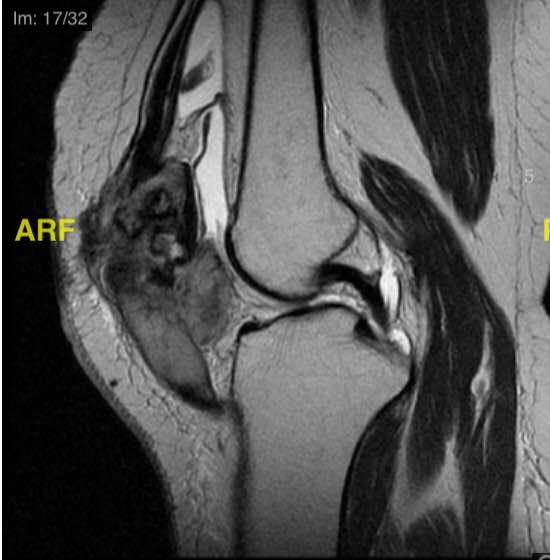

Patella Osteosarcoma